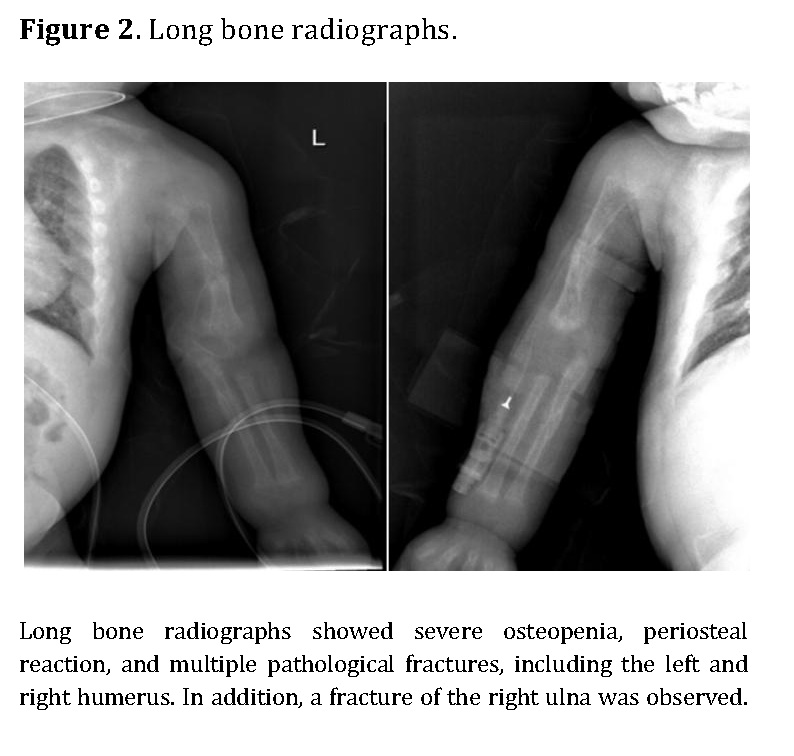

Chest radiography showed bilateral heterogeneous parenchymal infiltrates, pleural thickening, and right-sided rib fractures in the consolidation phase (Figure 1). Radiographs of long bones revealed severe osteopenia, periosteal reaction, and multiple pathological fractures, including the right and left humerus, right ulna, and right femur (Figures 2 and 3).